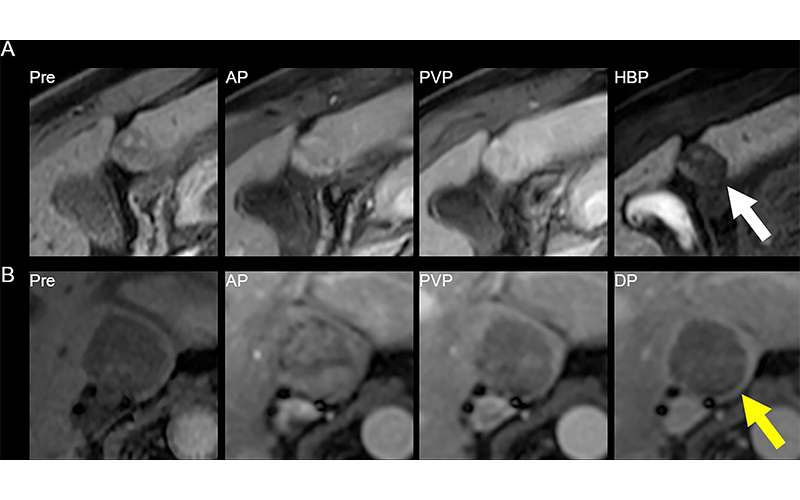

MRI scans show (A) reader disagreement and (B) reader agreement. (A) Gadoxetic acid–enhanced MRI scans in a 56-year-old male patient with cirrhosis secondary to hepatitis C. From left to right: contrast-unenhanced (Pre), arterial phase (AP), portal venous phase (PVP), and hepatobiliary phase (HBP) images. This 21-mm hepatobiliary phase hypointense observation (arrow) was characterized on the clinical read as having nonrim arterial phase hyperenhancement and washout appearance and was categorized as Liver Imaging Reporting and Data System (LI-RADS) category LR-5 (definitely hepatocellular carcinoma [HCC]). The first research reader characterized it as having a targetoid appearance and categorized it as LR-M (probably or definitely malignant, not specific for HCC). The second research reader characterized it as having no major features and paralleling the blood pool and categorized it as LR-2 (probably benign). It was subsequently resected and found to be a well-differentiated HCC. (B) Extracellular contrast–enhanced MRI scans in a 61-year-old female patient with cirrhosis secondary to hepatitis C. From left to right: contrast-unenhanced, arterial phase, portal venous phase, and delayed-phase (DP) images. This 31-mm observation (arrow) in the caudate lobe was characterized on the clinical read as having arterial phase hyperenhancement, washout appearance, and capsule appearance, and was categorized as LI-RADS category LR-5 (definitely HCC). Both research readers also categorized this observation as LR-5. The patient died of intracranial hemorrhage a few months later. https://doi.org/10.1148/radiol.222855 ©RSNA 2023